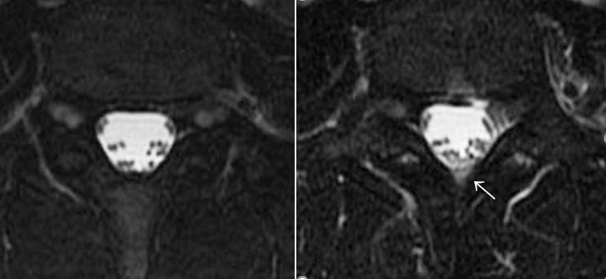

(1)iFDSS(incomplete FDSS):局所の微細(不完全)硬膜外水信号

「脳脊髄液漏出症診療指針」の画像診断基準における漏出確定・確実所見のみが脳脊髄液漏出症であり、それ以外の疑い例は診断否定のようにとられる場合が多い。しかし、これは明らかに誤解である。班研究の最終段階において、FDSSほど脊髄硬膜外水信号は明瞭ではないが、本病態に含まれると考えられる周辺病態の解析が進められた。解析結果を「非定型的所見」として「iFDSS:incomplete FDSS」という用語を用い、局所的な硬膜外微細水信号として髄液漏出の陽性所見とした。ただし、iFDSSは髄液貯留を示すものの、漏出部を示すものではない。

本所見が水信号とされた所以は、以下のとおりである。

班研究症例検討において、CTミエログラフィー・RI脳槽シンチグラフィー検査前後の脊髄MRI所見を観察したところ、検査のために行った腰椎穿刺部付近に穿刺前に認めなかった水信号が、穿刺後に観察される症例が複数あった。

すなわち腰椎穿刺による穿刺孔からの漏出と考えられる水信号である(下図矢印)。

したがって、このiFDSSが腰椎穿刺を行う前の脊髄MRIにて観察された場合には、硬膜外の水信号すなわち髄液漏出を考えるという考察が行われた。

また、令和2年2月第19回日本脳脊髄液減少症研究会(神戸)の特別講演にて、研究班画像診断担当の鹿戸先生(山形大学放射線診断科教授)に当院症例よりiFDSSの見本例を選定していただい画像の一部を載せる(図C)。このような所見を硬膜外腔の微細水信号(iFDSS)=脳脊髄液漏出所見と考えている。

図C

|